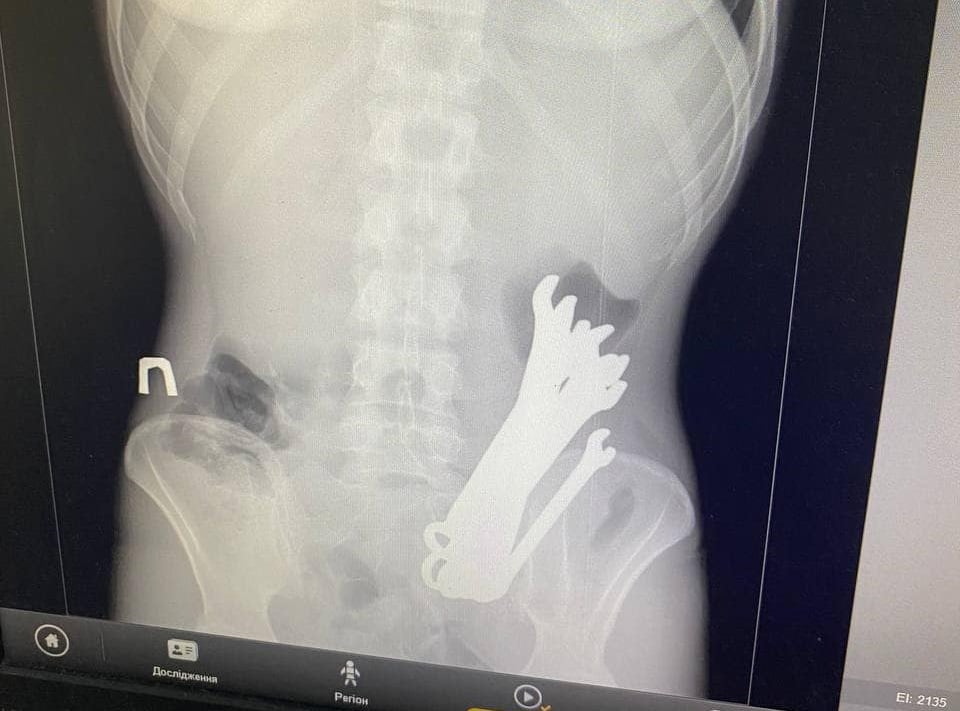

Черкаські лікарі дістали з пацієнта шість гайкових ключів

Про це розповіли у відділенні торакальної хірургії обласної лікарні. Інцидент стався у серпні. Пацієнта «К.» госпіталізували з флегмоною шиї,